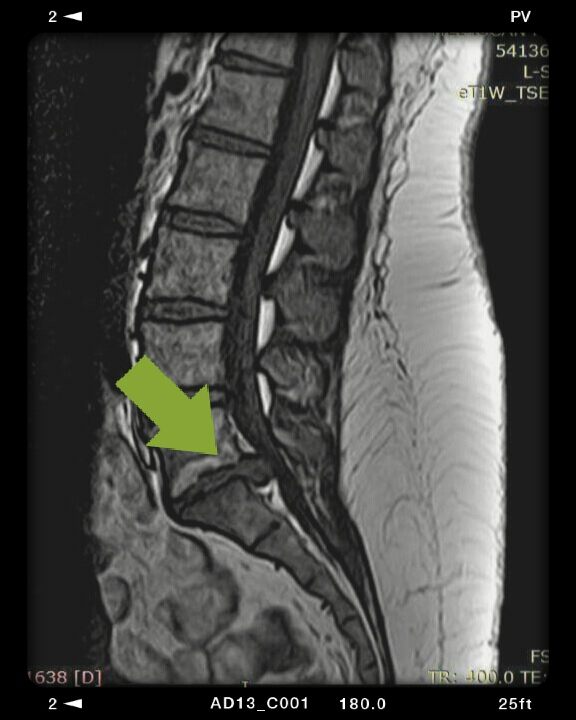

Οσφυϊκή δισκοκήλη Ο5Ι1.